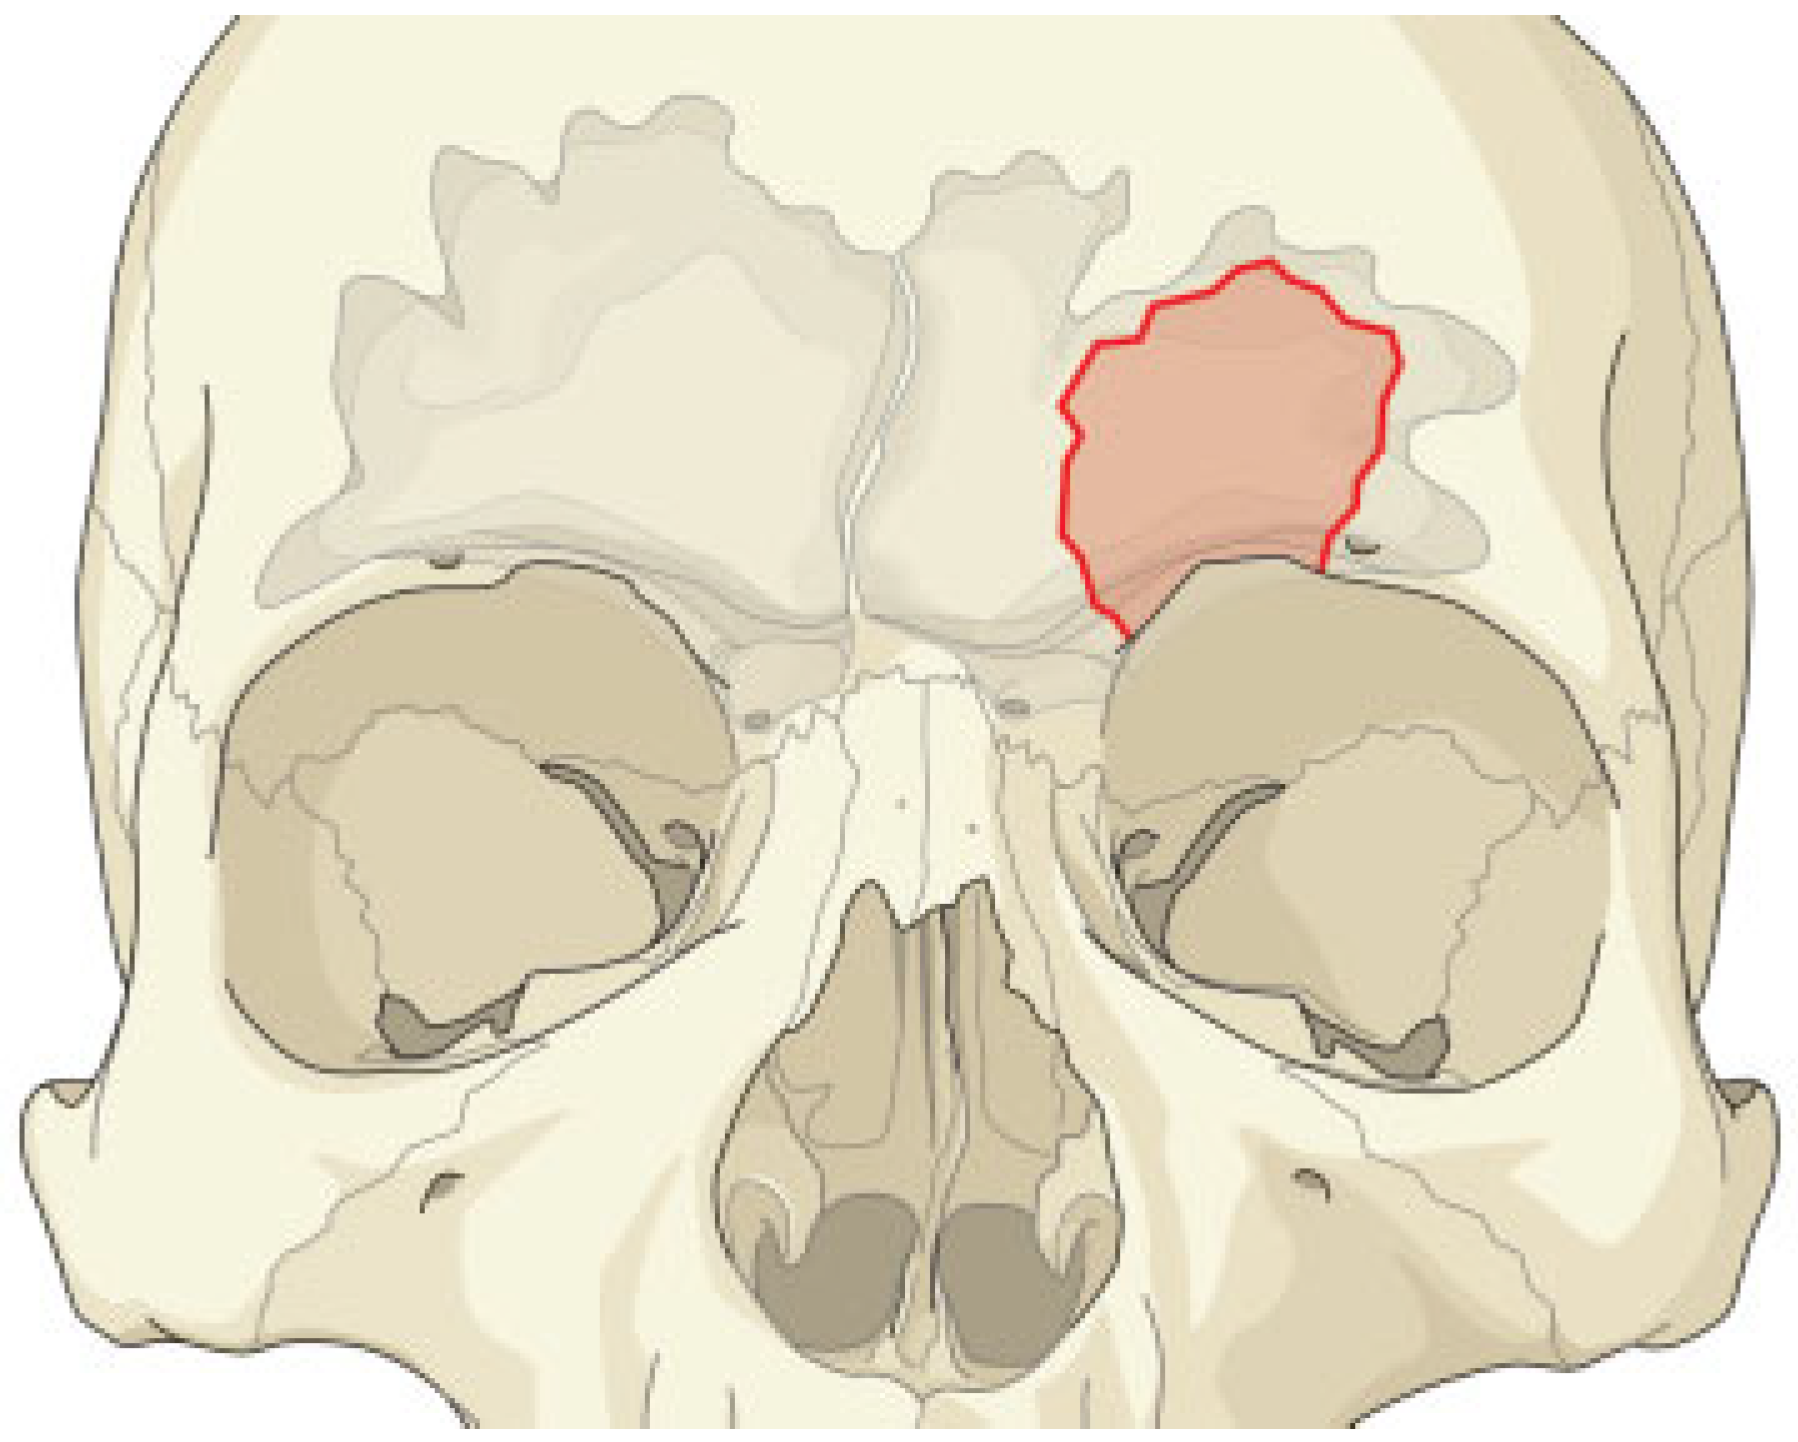

Open Surgical Management of an Asymptomatic Giant Frontal Sinus Osteoma

:Case Report